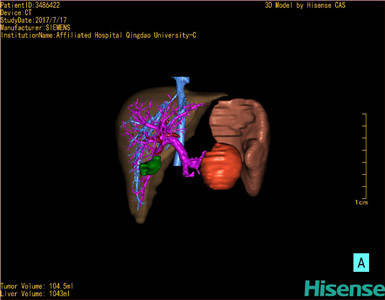

术前三维重建及手术方案设计:

将0.625mm双源薄层CT资料的静脉期和动脉期Dicom格式文件导入海信CAS系统。

通过调节窗宽窗位调整CT序号,对肿瘤,肝实质,胆囊,下腔静脉,肿瘤,肝动脉、门静脉及肝静脉等进行三维重建;系统自动计算肿瘤体积和肝脏体积。

模拟手术操作,自动计算切除肿瘤体积。肝脏体积为1096ml,胰腺肿瘤体积为115.5ml,通过比对12-13岁正常肝脏体积为1116.86±158.78 ml,通过术前模拟手术,精准判断切除后肝脏体积无明显变化,避免肝衰竭发生。

术前三维重建:

重建图片